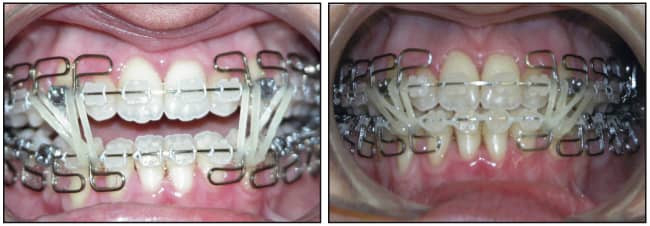

The posterior discrepancy was eliminated by extraction of the existing three third molars. Leveling and aligning took 6 months with the use of .014 and .016 Sentalloy archwires. Interferences to mandibular adaptation were eliminated by creating a posterior open bite. Mandibular adaptation occurred within 8 weeks as the anterior open bite closed and a Class I relationship was established (Figures 5 and 6).